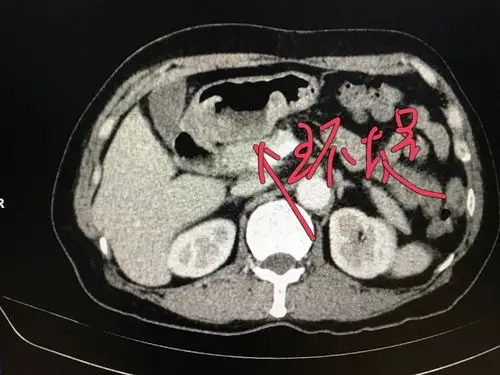

图3-41 胃溃疡型癌,钡餐检查,见腔外不规则龛影,有"环堤"及"指压迹"征

ct:肿瘤环堤征